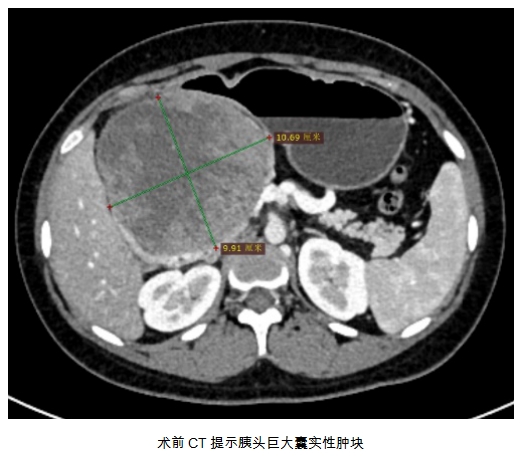

14岁女孩,应该在教室里听着课,跟同学们在操场上奔跑。李某却形单影只,不能参与到同龄人的活动,其父介绍近1年李某常常上腹疼痛,以为是...